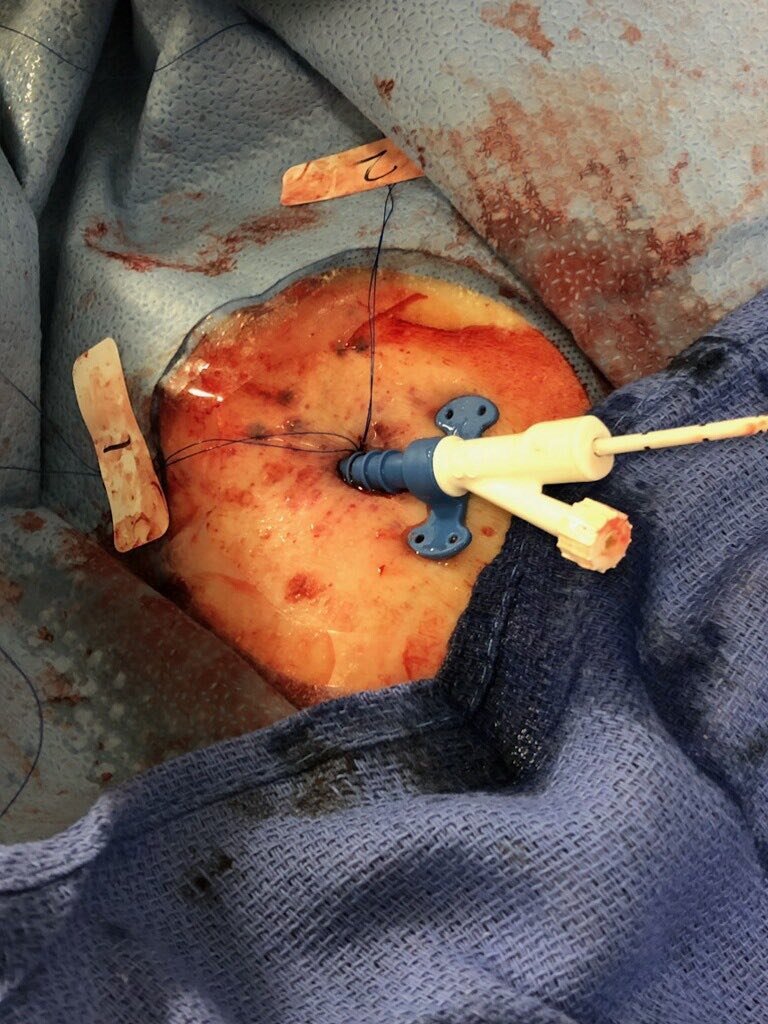

#PercAx #TAVR. Single Perclose. Dry closure. Post angio showed mild extravasation. Ten minutes manual pressure and repeat angio was pristine. No Perclose Pinch. No need for covered stent.

willsuh76's tweet image. #PercAx #TAVR. Single Perclose. Dry closure. Post angio showed mild extravasation.  Ten minutes manual pressure and repeat angio was pristine. No Perclose Pinch. No need for covered stent.